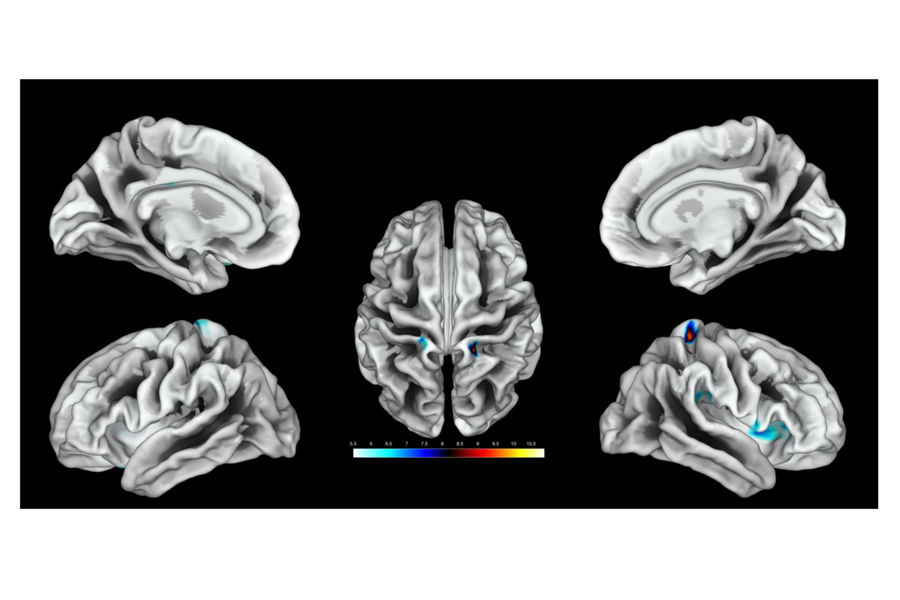

Как выяснилось, на стимуляцию гениталий реагируют области мозга, расположенные рядом с теми, что связаны с ощущениями от бедер — как и у мужчин. Но точная локализация у всех женщин была разной. У четверых, например, значительная активация наблюдалась лишь в левом или правом полушарии.

Также исследователи расспросили участниц об их половой жизни — когда они впервые занялись сексом и как часто делали это за последний год. Затем для каждой из них ученые определили десять наиболее выраженных точек в мозге, связанных со стимуляцией гениталий, и измерили плотность этих областей.

Как оказалось, у женщин, чаще занимавшихся сексом, эти области были развиты сильнее.

«Мы обнаружили связь между частотой половых контактов и толщиной индивидуально картированного генитального поля, — говорит Хейм. — Чем чаще секс, тем плотнее область».